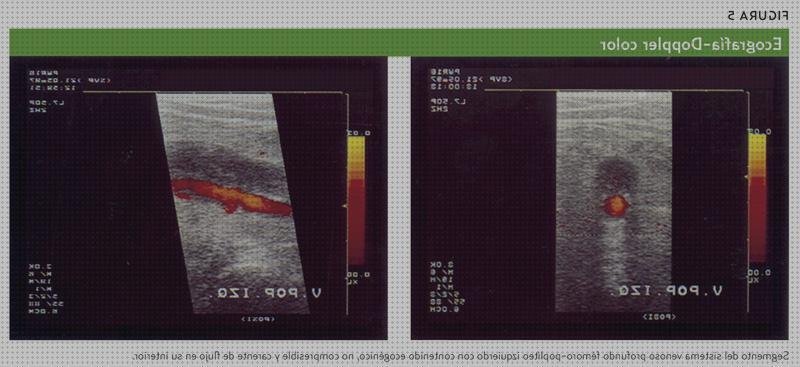

Científicos canadienses hallaron que aunque ninguna evidencia tiene una sensibilidad al cien%, la realización de ultrasonografías seriadas a lo largo de 7 días con técnico doppler en el vena iliaca excluye el diagnóstico de trombosis venosa profunda en mujeres embarazadas sintomáticas.